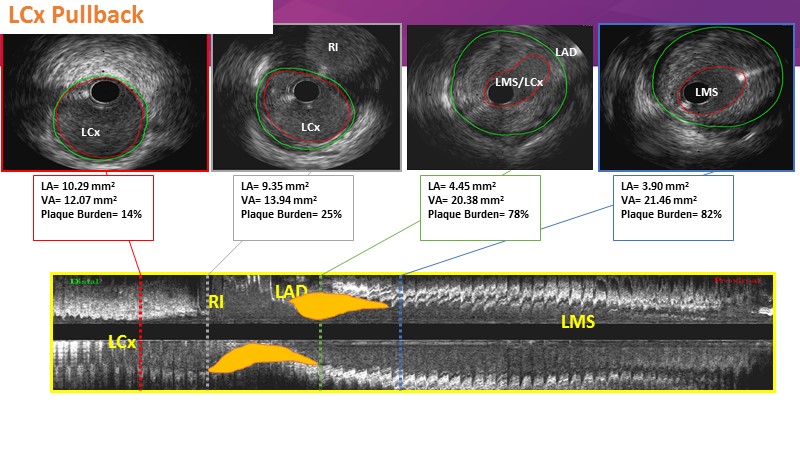

- To discuss contemporary treatment strategies for LMCA bifurcation lesions and to reflect on practical cases

- To explore state-of-the-art imaging on stent behaviour in bifurcation